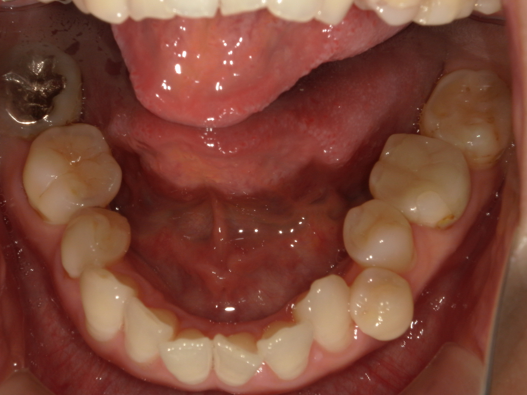

症例3:出っ歯が気になる

| 患者様データ | 20代 女性 |

| 来院主訴 | 出っ歯が気になる。 |

| 治療内容 | 出っ歯を治すために上の小臼歯を2本抜歯し、インビザラインにてマウスピース矯正を開始しました。かみ合わせを整えるためにゴムかけを行いました。 |

| 概算治療費 | 約85万円 |

| 治療期間 | 1年4ヶ月 |

| 通院回数 | 8回 |